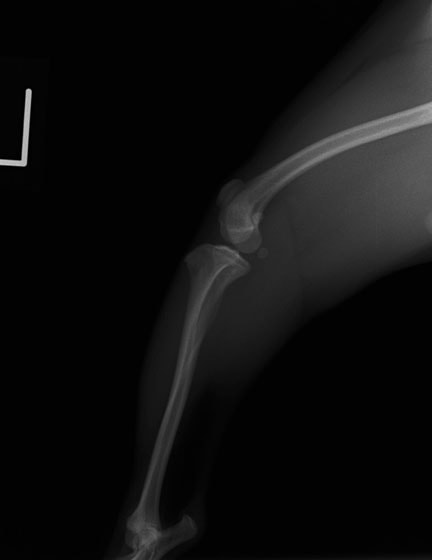

■ 症例24 キャバリア 7か月

左右膝蓋骨内方脱臼(左:グレードⅣ 右:グレードⅢ)

以前から左右後肢の跛行が認められ、整形外科学的検査・レントゲン検査により左右の膝蓋骨脱臼が認められた。症状が重度である左膝の膝蓋骨脱臼整復術を行った。外科手技は縫工筋及び内側広筋の解放、脛骨粗面の外側転位、滑車ブロック形造溝術、内外側関節方の縫縮を実施した。術後一か月時点で、左の膝蓋骨は安定しており経過は良好である。

本症例は成長期における重度の膝蓋骨脱臼であり、術後の再発の可能性もあるため、経過をしっかりと観察していく必要がある。また、今回手術を実施していない右膝に関しても経過を観察し、手術を検討していくこととする。